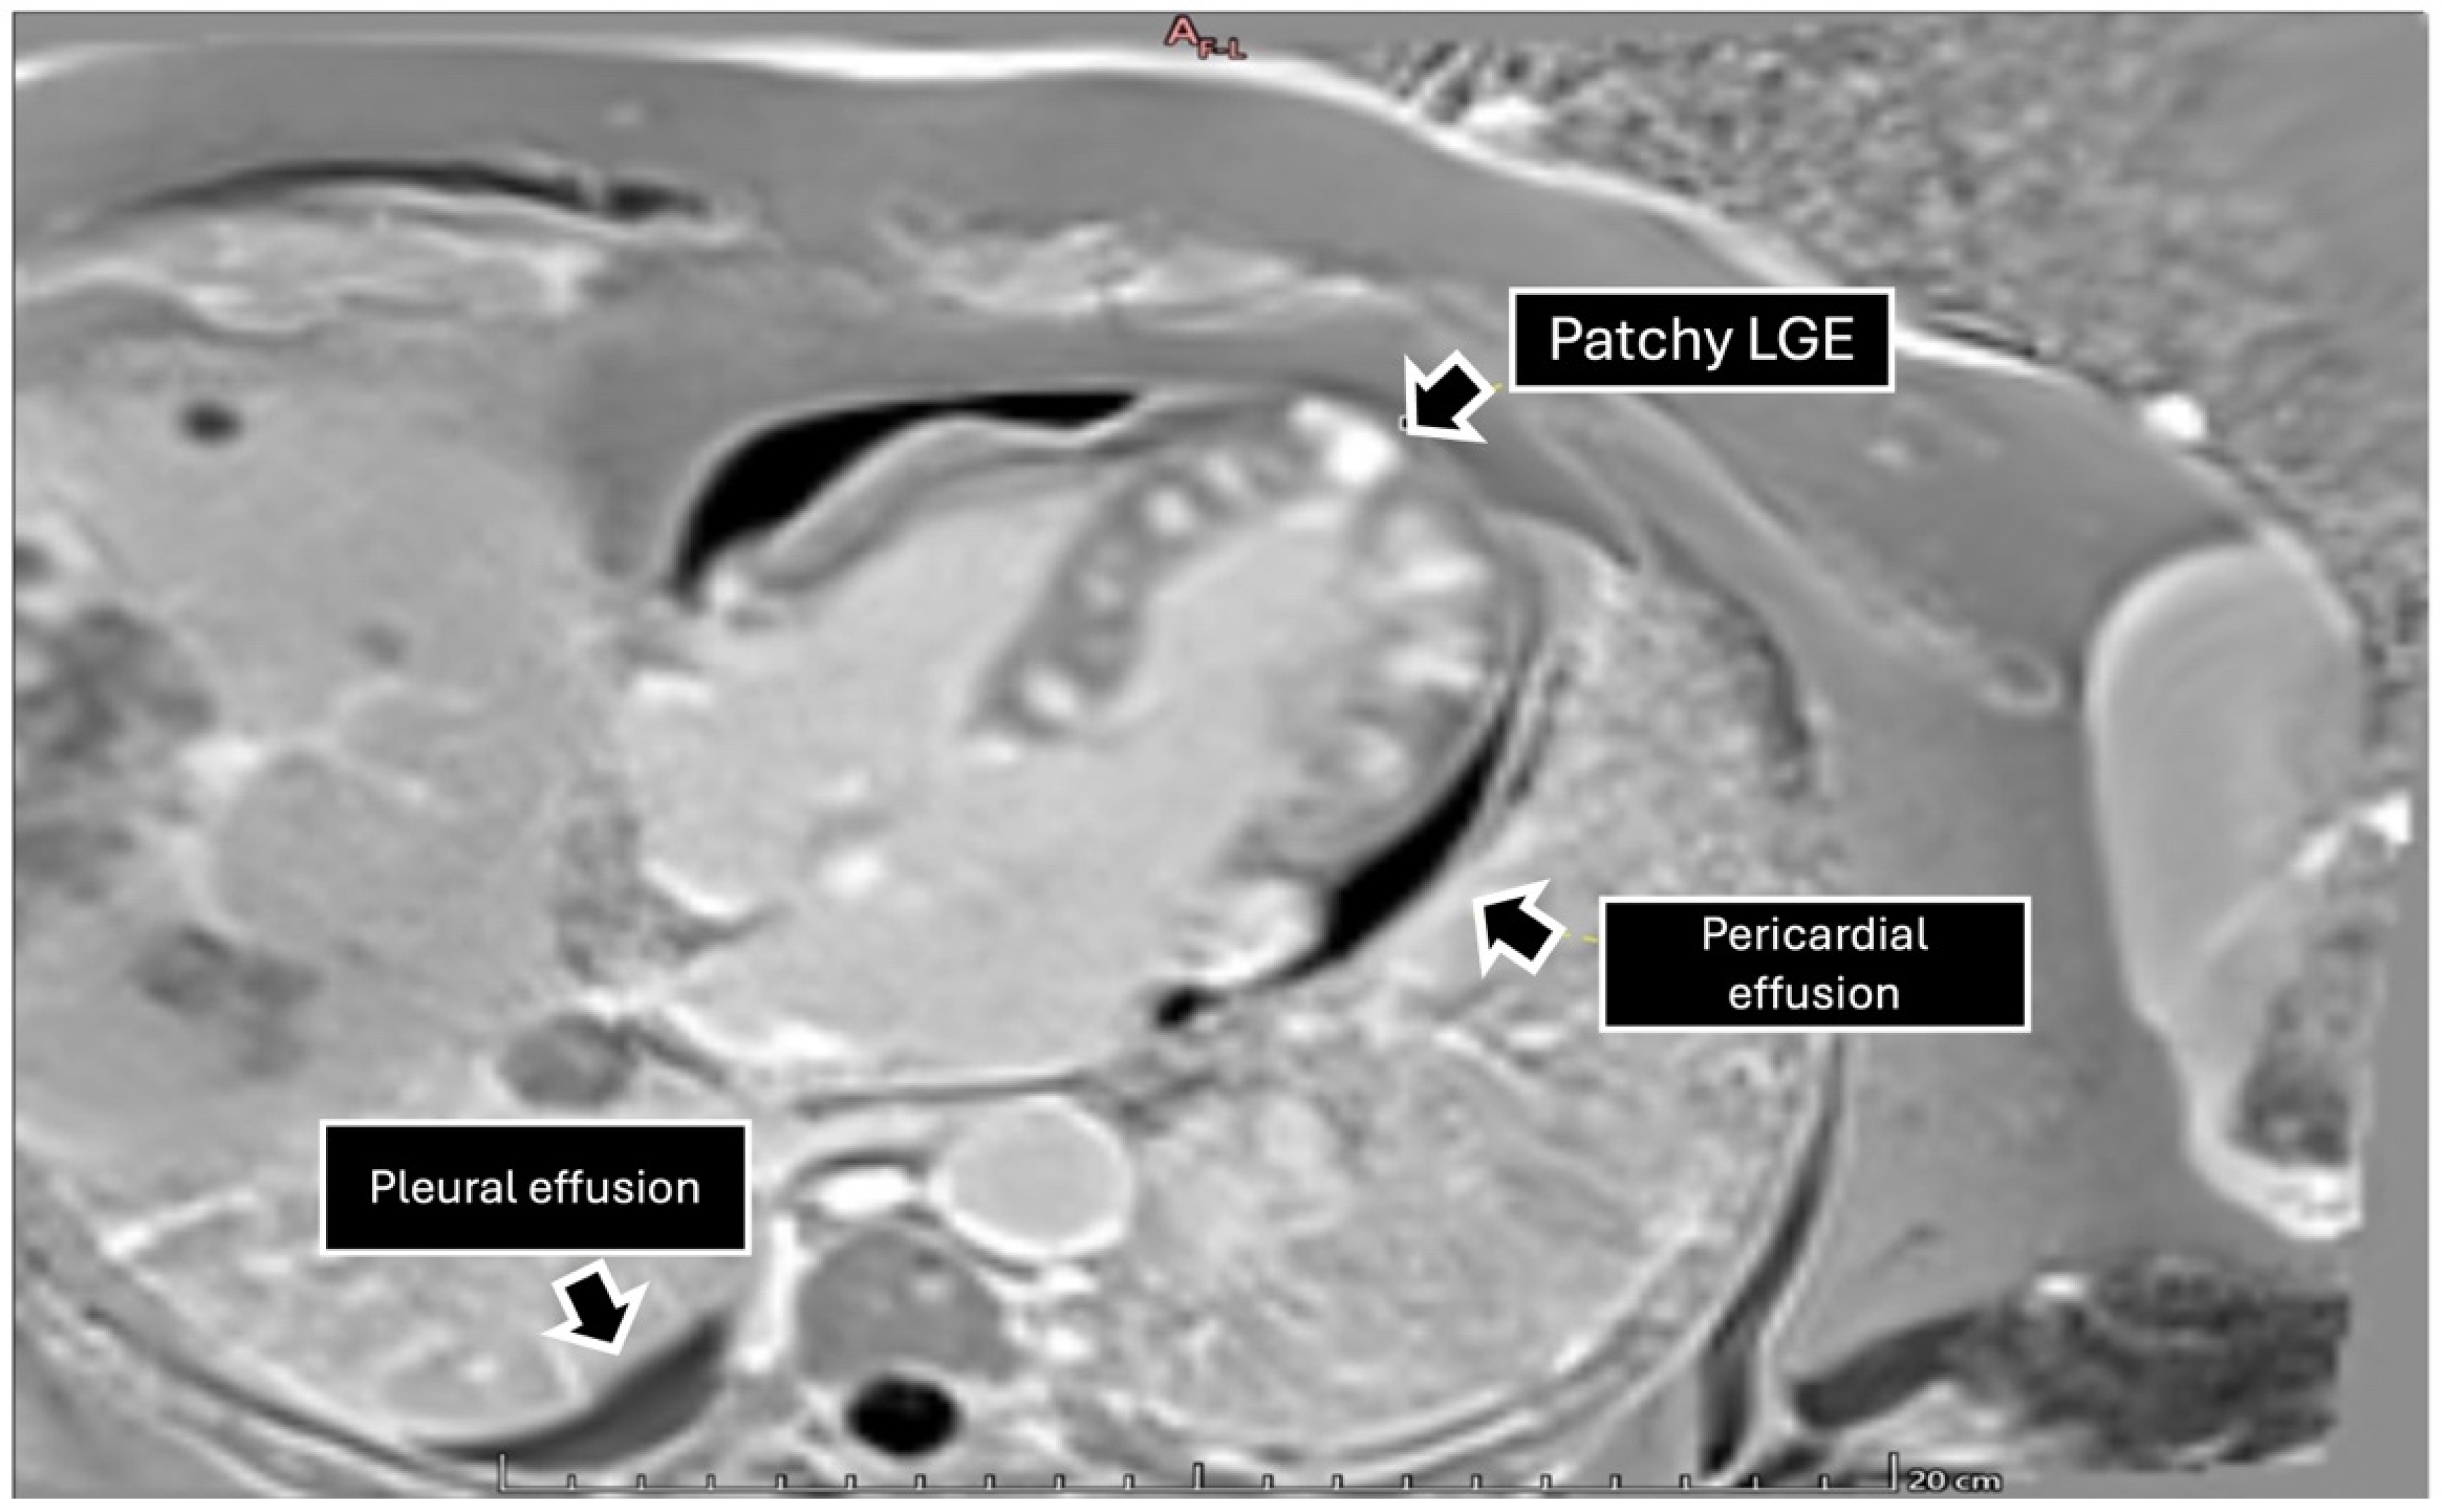

To further characterize the cardiac findings, we performed CMR, which demonstrated concentric left ventricular (LV) hypertrophy and normal global wall motion, with a preserved ejection fraction ≥70%. On T1-weighted sequences, heterogeneous cylindrical hyperintense regions with diffuse, ill-defined margins were observed throughout the LV myocardium, suggesting extensive infiltrative disease (Figure 2). Native T1 mapping revealed focal areas of low signal intensity, consistent with possible necrosis (Figure 3). Additionally, late gadolinium enhancement (LGE) demonstrated focal and diffuse predominantly mid-wall myocardial involvement, with heterogeneous gadolinium uptake in two-chamber and short-axis views, consistent with intramural necrosis and a non-coronary pattern, supporting metastatic infiltration rather than ischemic injury (Figure 4). It should be noted, however, that low native T1 values on CMR are not specific to cardiac melanoma metastases and may also be observed in other myocardial storage diseases, including myocardial iron/hemosiderin deposition and Anderson–Fabry disease [7]. Nevertheless, in the appropriate clinical context, a structured CMR-based assessment may provide incremental diagnostic value. In our patient, the CMR MASS score was 6 points, driven by infiltrative myocardial involvement, a polylobulated mass-like morphology, associated pericardial effusion, and early contrast enhancement. When low native T1 values were integrated with the patient’s oncologic history and systemic disease burden, these findings were consistent with malignant cardiac involvement.

Figure 3. Four-chamber view with late gadolinium enhancement sequence showing areas of diffuse enhancement in the left ventricular wall, especially in the atrioventricular groove corresponding to the right coronary artery territory. Pericardial thickening with a mild pericardial effusion is observed. Extended images toward the lung reveal multiple diffusely distributed tumors, as well as a small right pleural effusion.